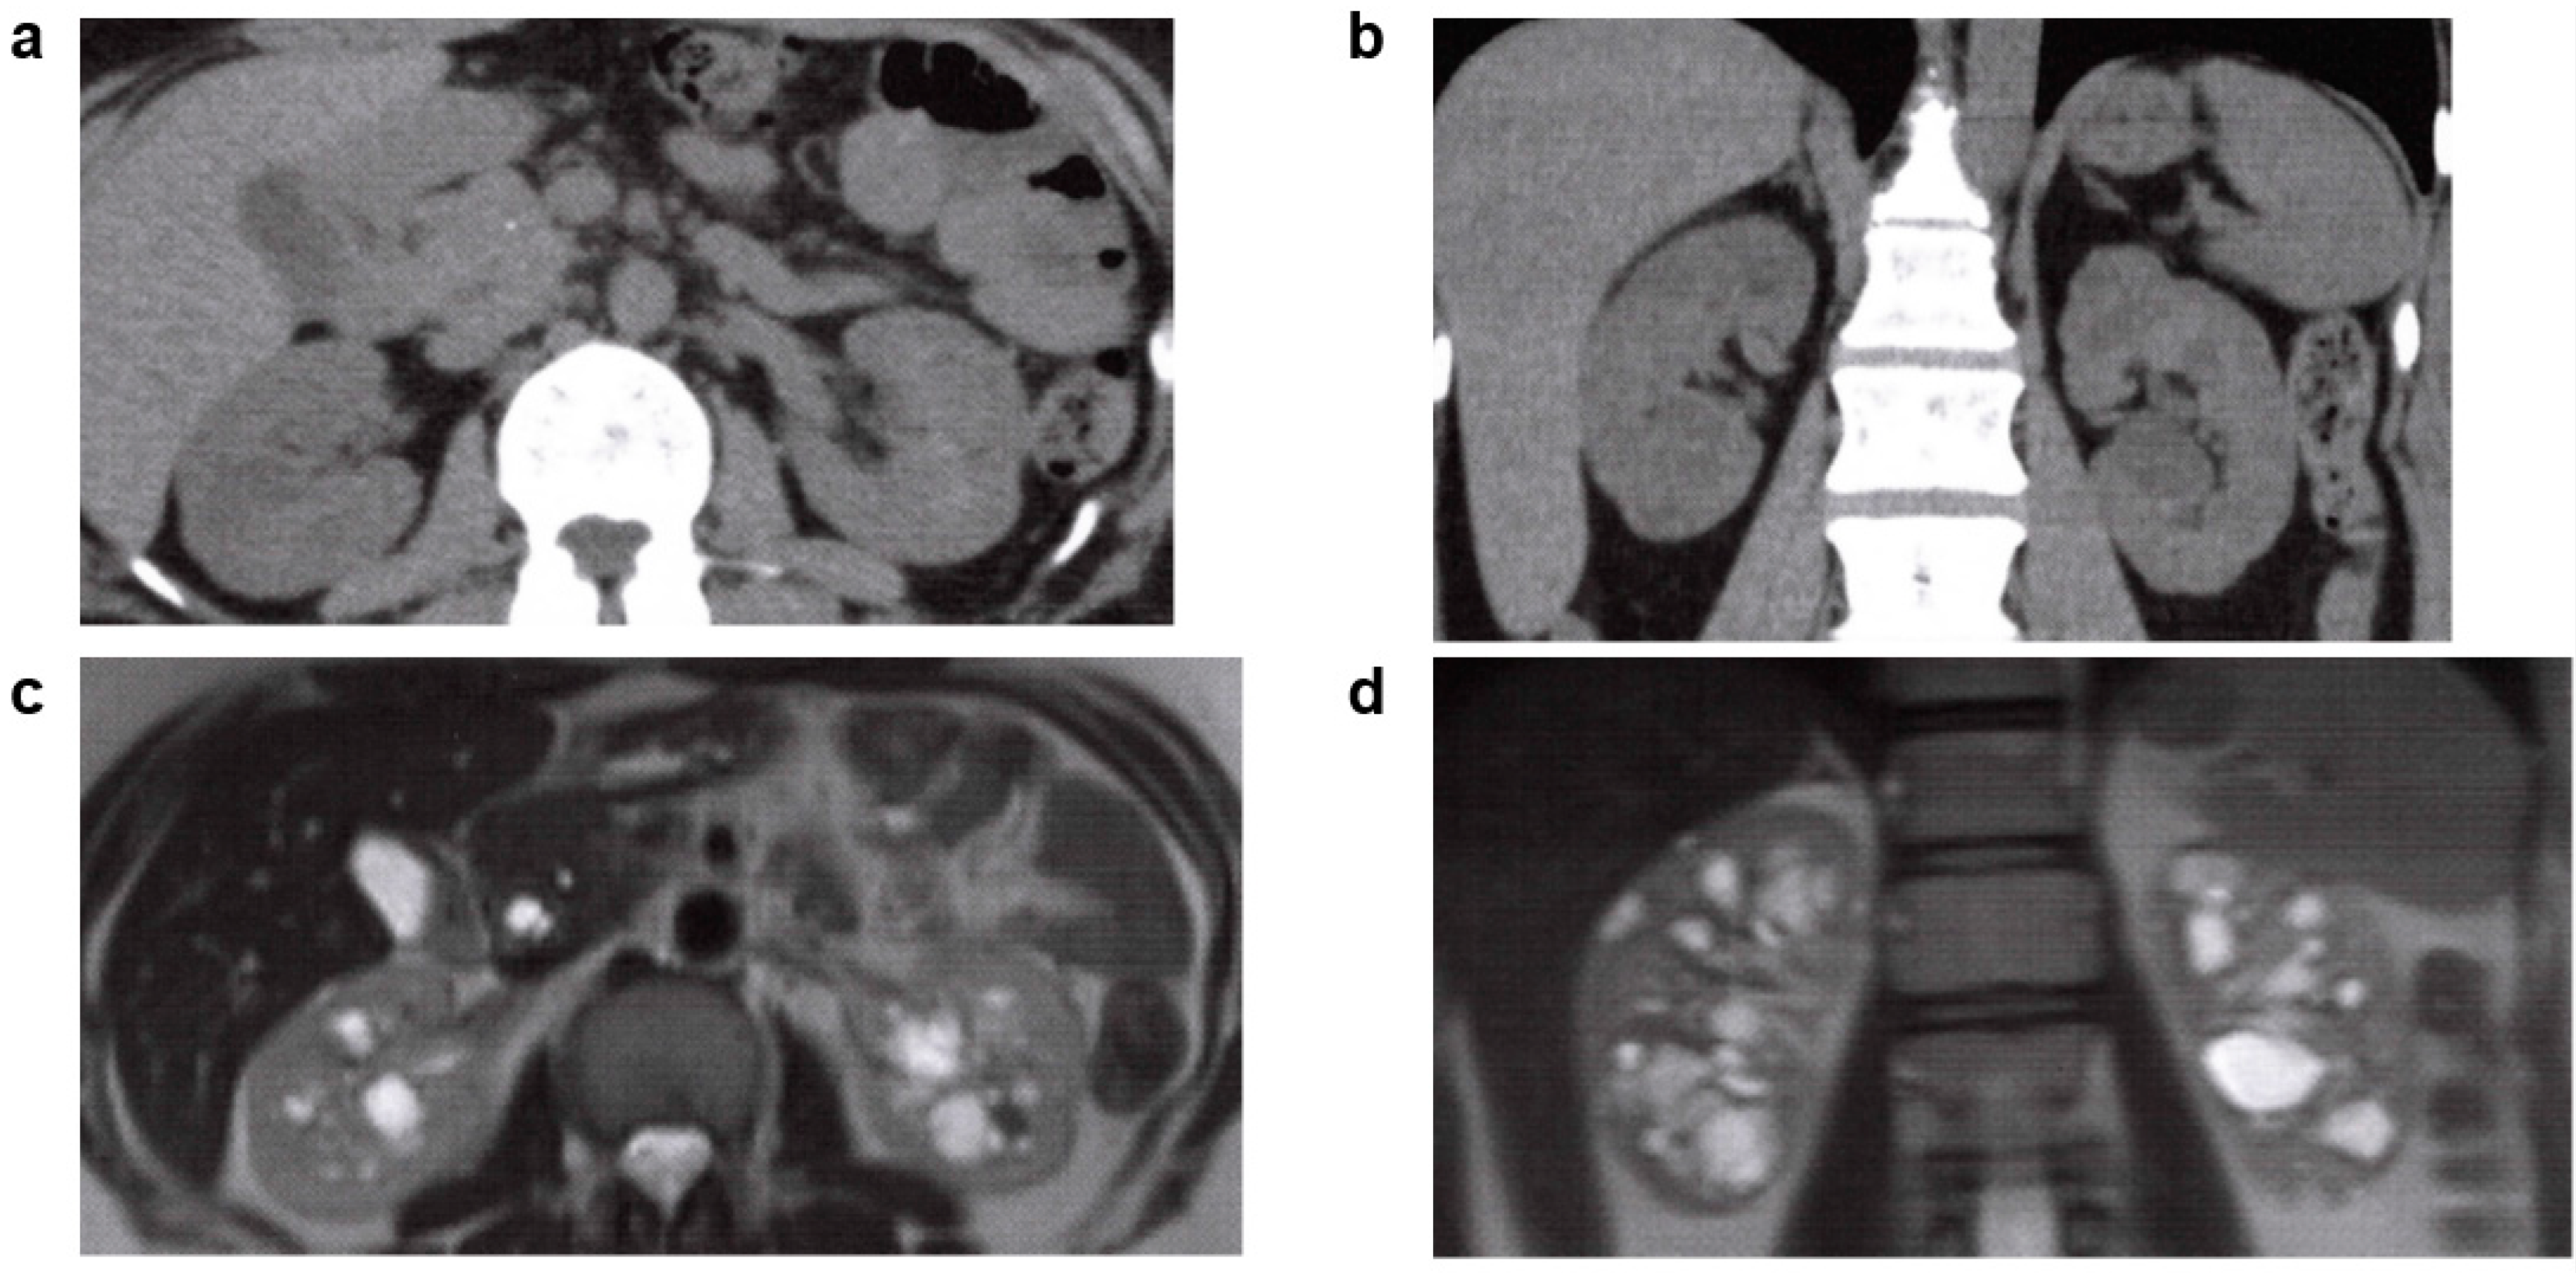

3.6.1. Tuberous Sclerosis (TSC)

| TSC | TSC1, TSC2 | AD | 1/10,000 | Hamartoma in the skin, nervous system, kidney, lung, bone, and elsewhere. Renal lesions; angiomyolipoma (AML), renal cysts, renal cell carcinoma. |